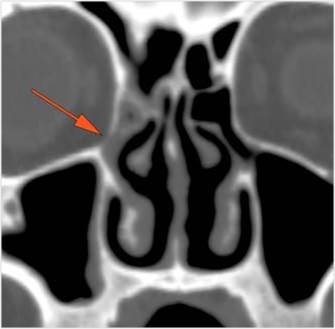

The extraconal orbital fat surrounding the infraorbital vascular bundle is infiltrated